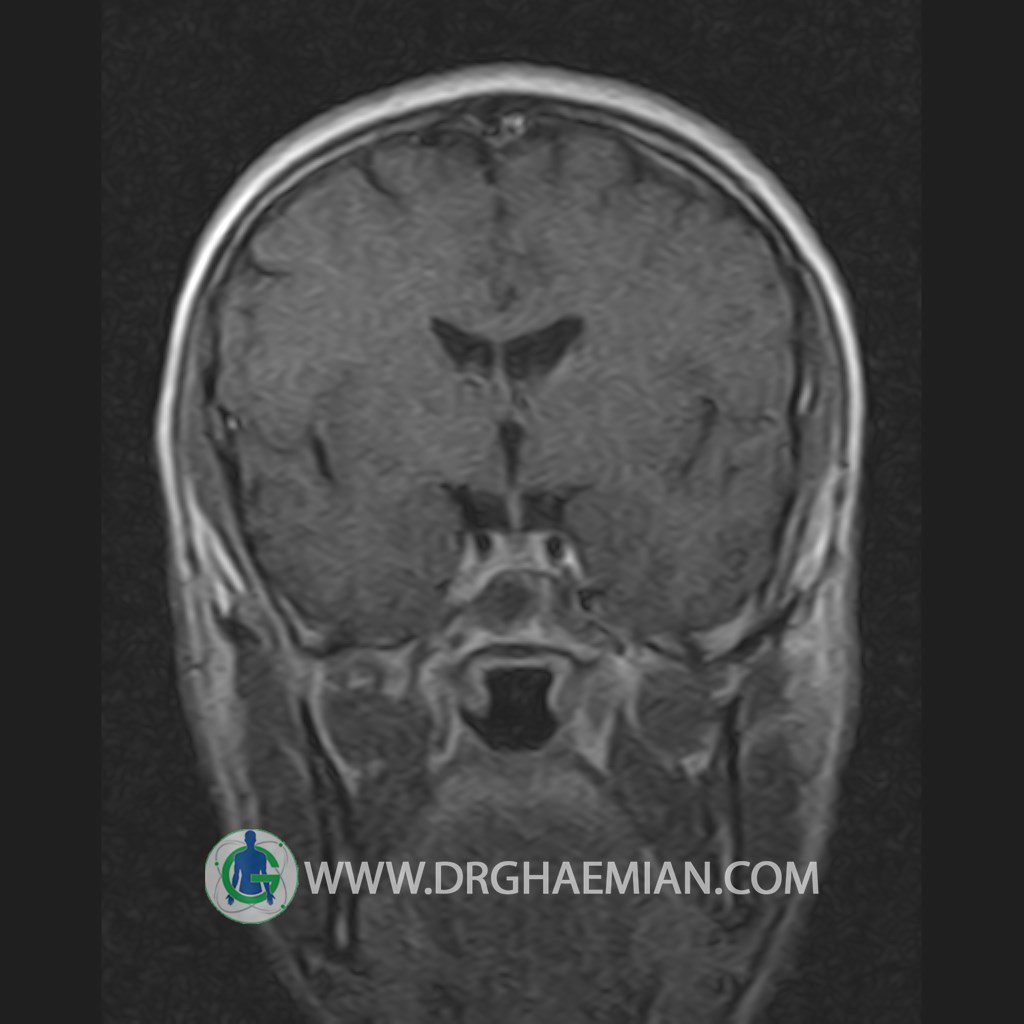

پزشکان اغلب از تصویربرداری ام آر آی برای تشخیص و درمان عارضه های پزشکی که فقط با استفاده از اشعه ایکس یا میدان مغناطیسی و امواج رادیویی قابل مشاهده است، استفاده می کنند. دستگاه ام آر آی تصاویر دقیق از ساختار های داخلی بدن ایجاد می کند. در این کیس یک میکروآدنوم در هیپوفیز بیمار مشاهده می شود.

HYPOPHYSIS MRI

(with and without contrast)

Technique: Axial , coronal T1 , Axial , coronal , sagittal T2 , Axial, coronal T1 post Gd & 64 dynamic thin coronal slices.

REPORT :

The infundibulum is centered and of normal size .

The optic chiasm and suprasellar spaces appear normal .

The cavernous sinus and imaged portions of the internal carotid artery and carotid siphon are unremarkable .

Evaluable portions of the neurocranium show no abnormalities .

The sphenoid sinus is clear and pneumatized .

Imaging of the hypothalamus after contrast medium administration was normal.

– Small hypoenhancing mass lesion ( 3 x 4 mm ) in posterior of pituitary stalk suggestive for micro adenoma

– Mucosal thickening in ethmoid & maxillary sinuses

is seen